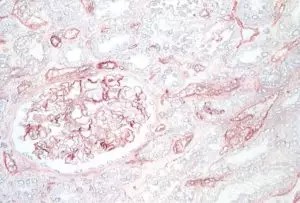

C4d Function Circulating alloantibodies encounter the grafted endothelium as the first target. Living endothelial cells can rapidly eliminate bound antibodies from the cell surface by “capping”, “shedding” or “internalisation”. C4d is the degradation product of the activated complement factor C4, a component of the classical complement cascade, which is typically initiated by binding of antibodies to specific target molecules. Detection of C4d is regarded as an indirect sign, a “footprint” of an antibody response against the allograft. The majority of publications describe C4d as an important biomarker in kidney transplantation but also in heart, liver, and other transplants.